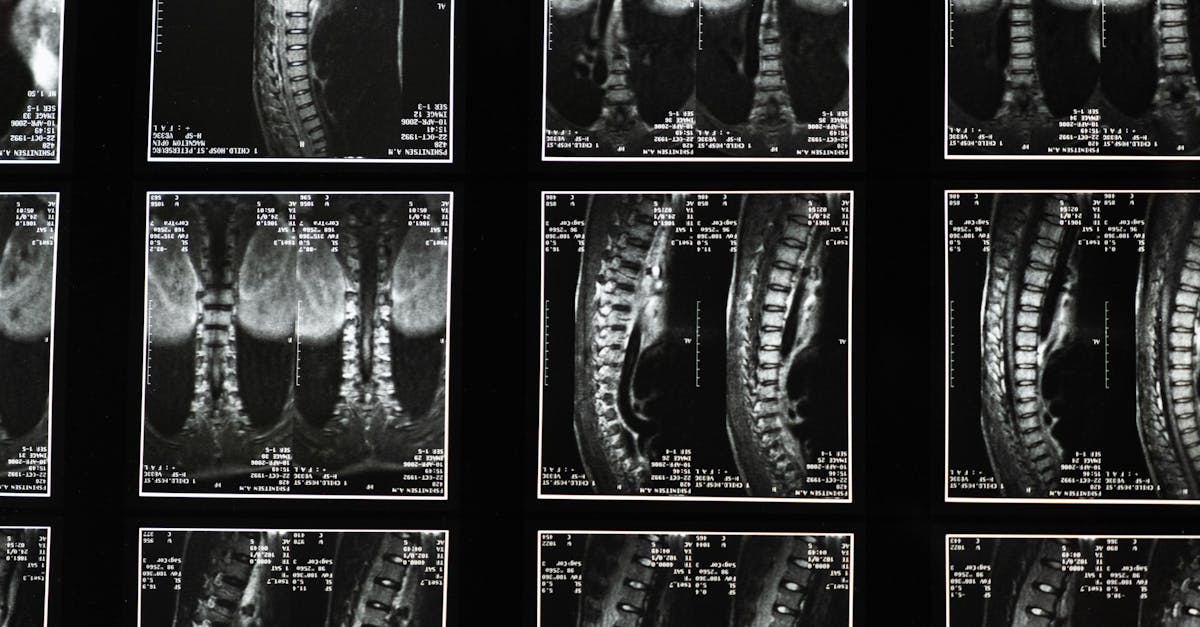

La décompression neurovertébrale est une procédure visant à réduire la pression sur la moelle épinière et les nerfs grâce à des techniques non invasives. Cette méthode est particulièrement efficace pour traiter des problèmes tels que les hernies discales, les pincements nerveux, et d’autres conditions qui causent des douleurs chroniques. En utilisant des techniques de traction mécanique, elle crée de l’espace entre les disques intervertébraux, ce qui permet de diminuer la douleur et d’améliorer la mobilité.

La décompression neurovertébrale repose sur la traction mécanique, qui consiste à créer un espace entre les disques intervertébraux. Cela permet de réduire la pression sur les nerfs et la moelle épinière, soulageant ainsi les symptômes associés aux pathologies dorsales. Les techniques employées peuvent varier, incluant l’utilisation de tables spécialisées ou des appareils de traction, et sont généralement adaptées aux besoins spécifiques de chaque patient.

Parmi les nombreux bienfaits de la décompression neurovertébrale, on retrouve la réduction de la douleur et l’amélioration de la mobilité. En libérant la pression sur les nerfs engendrée par des disques intervertébraux abîmés ou protrusés, cette méthode contribue à atténuer les inflammations et à stimuler la circulation sanguine dans les zones affectées. L’augmentation de la circulation peut également favoriser la guérison des tissus et aider à restaurer la fonction nerveuse optimale.

Le traitement par décompression neurovertébrale fonctionne grâce à des techniques de traction mécanique, visant à élargir l’espace entre les disques intervertébraux. Ce processus non chirurgical réduit la pression sur les nerfs et favorise la circulation sanguine dans les zones touchées, contribuant ainsi à une meilleure récupération et un soulagement durable des douleurs. Des études ont démontré son efficacité pour traiter des affections telles que la dégénérescence discale et les inflammations des racines nerveuses, en apportant une réponse adaptée aux besoins spécifiques de chaque patient.